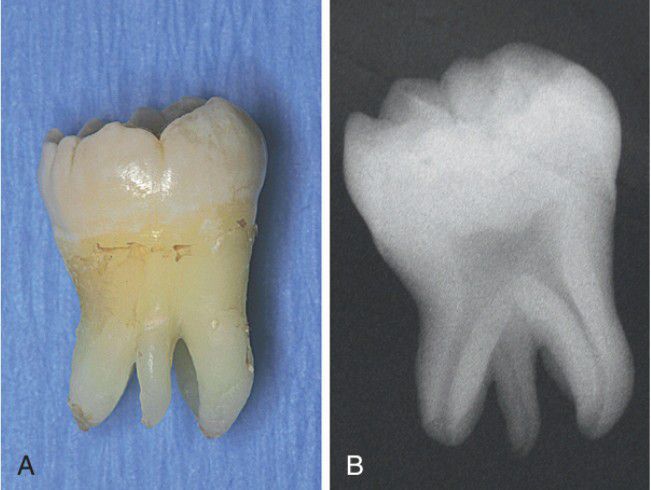

Supernumerary root

Supernumerary Root. A, Gross photograph showing a mandibular molar with a supernumerary root. B, Periapical radiograph of the extracted to